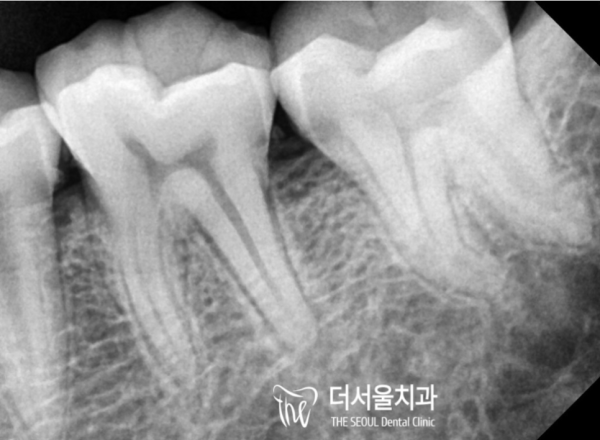

때문에 환자분들의 치아상태를 정확히 파악하기 위해서는

엑스레이 촬영을 통해 눈에 보이지않는 부분을 확인해야합니다.

So, in order to accurately understand the condition of the patients' teeth

You should check the invisible part through X-rays.

치아 내부를 확인해본 결과 치수강 근처까지 감염이 진행된것을

확인할 수 있었습니다.

I checked the inside of the tooth and found that the infection had spread to the vicinity of the suprachial cavity

I was able to check it.